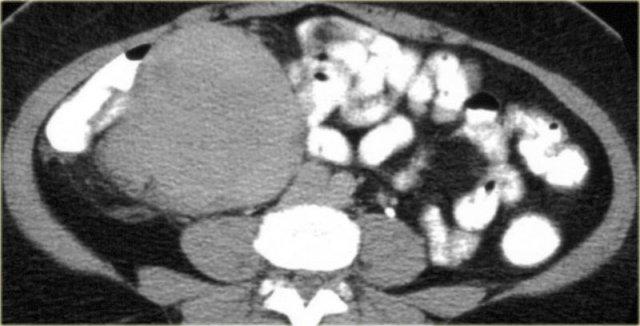

Trước hết, đây là tổn thương có bờ rõ với giảm tỷ trọng trên CT.

Có ngấm thuốc nhẹ xung quanh tổn thương và một số dải ngấm thuốc nhỏ bên trong tổn thương.

Trên MRI, tổn thương giảm tín hiệu trên chuỗi xung T1W như dự kiến.

Trên chuỗi xung T2W, tổn thương tăng tín hiệu tương đối.

Kết hợp với giảm tỷ trọng trên CT, điều này cho thấy có chứa mucin bên trong tổn thương.

Đặc điểm này rất gợi ý chẩn đoán u xơ mạc treo.

Mức độ ngấm thuốc trên MRI rõ hơn so với trên CT.

Trên CT, giảm tỷ trọng của mucin nổi bật hơn, nhưng trên MRI chúng ta có thể đánh giá sự ngấm thuốc tốt hơn.

Điều này cho thấy tổn thương được tưới máu tốt.

U xơ mạc treo hay u desmoid là quá trình tăng sinh lành tính, xâm lấn tại chỗ và có thể tái phát, nhưng không di căn.

Mạc treo ruột non là vị trí thường gặp nhất.

13% bệnh nhân có đa polyp tuyến gia đình (FAP).